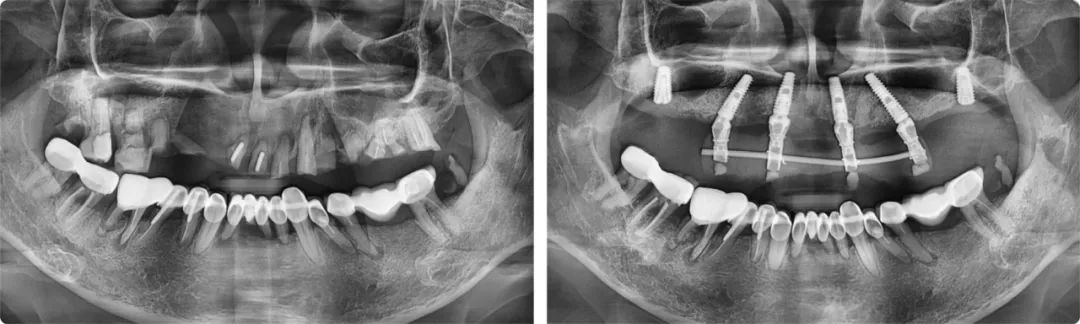

今年五月,葉宏接診了一位56歲的患者。這位患者的上半口全是牙齒殘根,骨量也不好,種植點位非常難選。一般情況下,上頜骨有6-8毫米的高度就可以滿足種植條件,但患者只有2-3毫米,風險較大,且種植位置靠近上頜竇,需要采用斜行植體,穿過兩個牙位,備孔時要斜著鉆,非??简炨t(yī)生的技術水平和臨床經(jīng)驗。

為力求最佳的治療效果,葉宏為患者制訂了個性化的治療方案。“這例上半口種植由于情況特殊,不能一次性完成六顆牙的種植,我分了兩步完成。第一步是即拔即種,種4顆,然后清創(chuàng),等待恢復,三個月后完成第二步,補種兩顆。”

患者術前術后全景片

葉宏解釋了這樣做的原因:標準的無牙頜種植上頜一般是6-8顆,下頜4-6顆,如果口腔條件允許,他會建議患者至少要種六顆,這樣牙槽骨受力更加均勻。如果只種四顆,后期的維護成本相對較高。分兩步走的治療方案雖然麻煩一些,但保障了種植牙的遠離穩(wěn)定性。